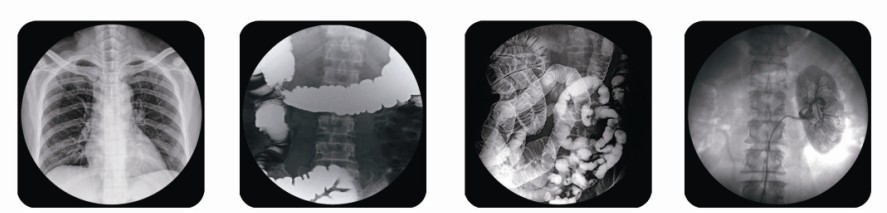

或許有一些患者會為醫(yī)院的醫(yī)療設(shè)備感到奇怪,奇怪什么呢?那就是去醫(yī)院看病的人這么多,大部分人的病情也不一樣,但感覺醫(yī)院的醫(yī)療設(shè)備沒有想象的那么多。其實這是由于現(xiàn)代醫(yī)療行業(yè)發(fā)達(dá),醫(yī)療器械的技術(shù)先進(jìn)使一機(jī)多用的機(jī)器越來越多了。其中也包含了x線胃腸機(jī)設(shè)備。x線胃腸機(jī)俗稱胃腸機(jī),主要用于檢測患者胃腸道及膽道、泌尿道造影以及下肢靜脈造影,可透視下進(jìn)行骨折整復(fù)、取異物等工作,總之功能多多。

在此需要向大家介紹的是普朗醫(yī)療公司,普朗醫(yī)療是國內(nèi)專業(yè)從事生產(chǎn)經(jīng)營醫(yī)療器械產(chǎn)品的公司,普朗公司生產(chǎn)的x線胃腸機(jī)有九個型號可供用戶選購,下面以PLD5800 x線胃腸機(jī)向大家介紹一下該產(chǎn)品的部分特點。PLD5800 x線胃腸機(jī)采用高品質(zhì)東芝影像增強(qiáng)器和進(jìn)口超低照度數(shù)碼攝像機(jī)(CCD,并配備數(shù)字圖像處理系統(tǒng),具備8幅圖像存儲、圖像降噪、鏡像翻轉(zhuǎn)、正負(fù)圖像、末幀凍結(jié)等功能,輸出逐行高清晰度的電視透視圖像,低噪音、對比豐富、高質(zhì)量,同時避免了圖像邊緣衰減、影像拖尾等現(xiàn)象,便于在動態(tài)觀察時準(zhǔn)確診斷直觀顯示的人機(jī)界面,采用觸摸屏控制技術(shù),使人機(jī)對話更加直觀,方便,易懂。總而言之,普朗的x線胃腸機(jī)優(yōu)點非常多,是廣大用戶的首選品牌產(chǎn)品。

(普朗醫(yī)療品牌——高頻醫(yī)用診斷X射線機(jī)PLD5800x線胃腸機(jī)))